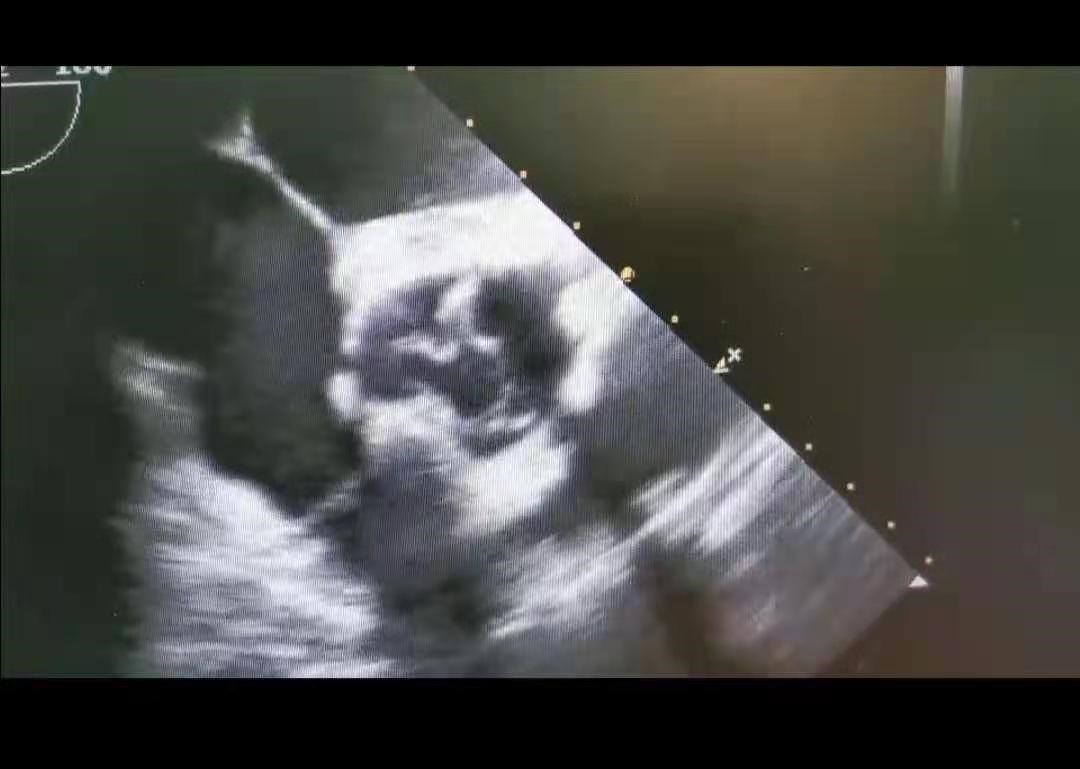

术后复查超声显示再造的主动脉瓣启闭良好,狭窄及关闭不全消失,病人于术后1周即顺利出院。